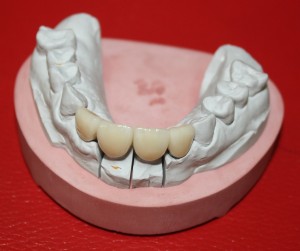

Через три месяца мы сняли коронки с имплантатов, чтобы оценить качество формирования десневого контура:

С этого момента можно перестать переживать — десневой контур сформировался правильно, мы получили достаточный объём и качество окружающей платформу имплантата десны. Можно приступать к изготовлению постоянной протетики. Подрядчиком стала зуботехническая лаборатория French Creative, одна из топовых лабораторий Москвы.

На фотографиях с временными коронками, — я уверен, вы обратили на это внимание, — шахты фиксирующих винтов выходят на режущий край:

Поэтому для постоянных протетических конструкций мы выбрали цементную фиксацию на индивидуальных абатментах.

На первом этапе зафиксировали и индивидуализировали трансферы, с помощь которых положение имплантатов переносится в гипсовую модель:

затем сняли оттиски и передали из в зуботехническую лабораторию. Кстати, на этом этапе мы также рекомендуем делать прицельные снимки для контроля посадки трансферов.